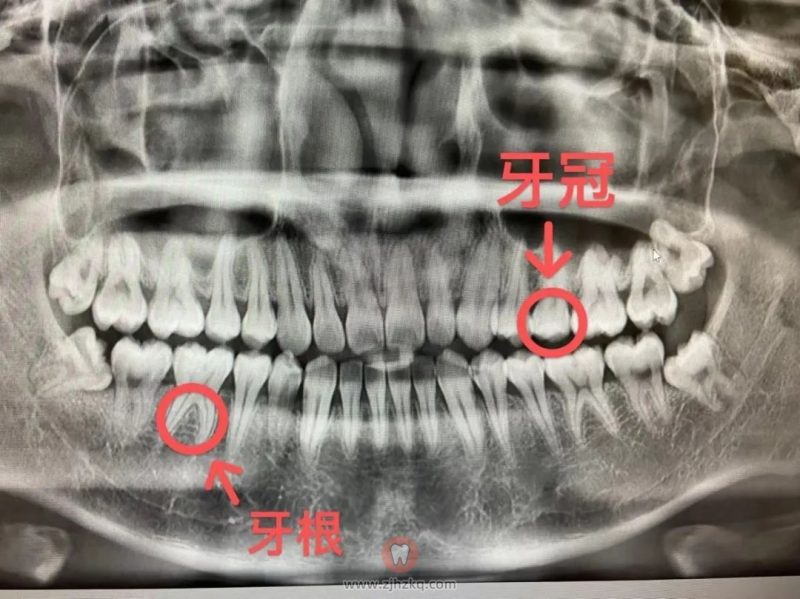

拍牙片算不算额外消费过度医疗 杭城看牙记 • 2023年3月4日 20:00 • 看牙问答 想必很多去看牙的杭州朋友,都有过面诊完医生之后,就被带去拍牙片的经历,不少人在心里嘀咕:医生还没有跟我说得很明白,怎么就要拍牙片了?钱包又要留不住了? 我们平时可以看到的露在外面的牙齿部分叫做牙冠,牙根是看不到的。 但是有些牙齿,整颗还没有来得及长出来,或者说长在普通视角很难发现的位置,这个时候就需要依靠牙片来发现这些“隐藏牙”了。 像拔智齿、补牙、根管治疗、牙周病、种植牙、牙齿矫正等都需要进行拍片检查。 本文内容源自网络仅供参考,不作为诊断医疗依据,更多查询请 → 在线咨询客服